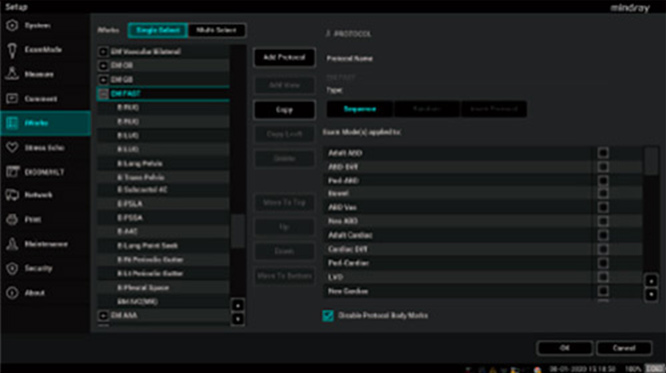

Acil servis personeli ĂŒzerindeki bask?y? azaltmak, klinik karar alma h?z?n? ve do?rulu?unu art?rmak ve hastalar?n ya?amlar?n? daha da garanti alt?na almak i?in. ME Serisi bak?m noktas? ultrasonunu, acil servis i? ak???n? g?z ?nĂŒnde bulundurarak tasarlad?k. Tek t?klamayla ge?i? i?in en s?k kullan?lan problara ve tarama i? ak??lar?na ?ncelik vermek ĂŒzere kullan?c? tan?ml? ayarlar sa?lan?r ve doktorlar?n acil durumlarda hasta durumunu yeterli ve h?zl? bir ?ekilde de?erlendirmesine olanak tan?mak i?in, FAST ve EFATE gibi ?e?itli h?zl? hasta ba?? ultrason protokolleri sistemde mevcuttur.

Mindray'in bak?m noktas? ultrasonunda acil muayeneler i?in protokoller.

Acil servis personeli ĂŒzerindeki bask?y? azaltmak, klinik karar alma h?z?n? ve do?rulu?unu art?rmak ve hastalar?n ya?amlar?n? daha da garanti alt?na almak i?in. ME Serisi bak?m noktas? ultrasonunu, acil servis i? ak???n? g?z ?nĂŒnde bulundurarak tasarlad?k. Tek t?klamayla ge?i? i?in en s?k kullan?lan problara ve tarama i? ak??lar?na ?ncelik vermek ĂŒzere kullan?c? tan?ml? ayarlar sa?lan?r ve doktorlar?n acil durumlarda hasta durumunu yeterli ve h?zl? bir ?ekilde de?erlendirmesine olanak tan?mak i?in, FAST ve EFATE gibi ?e?itli h?zl? hasta ba?? ultrason protokolleri sistemde mevcuttur.

Mindray'in bak?m noktas? ultrasonunda acil muayeneler i?in protokoller.